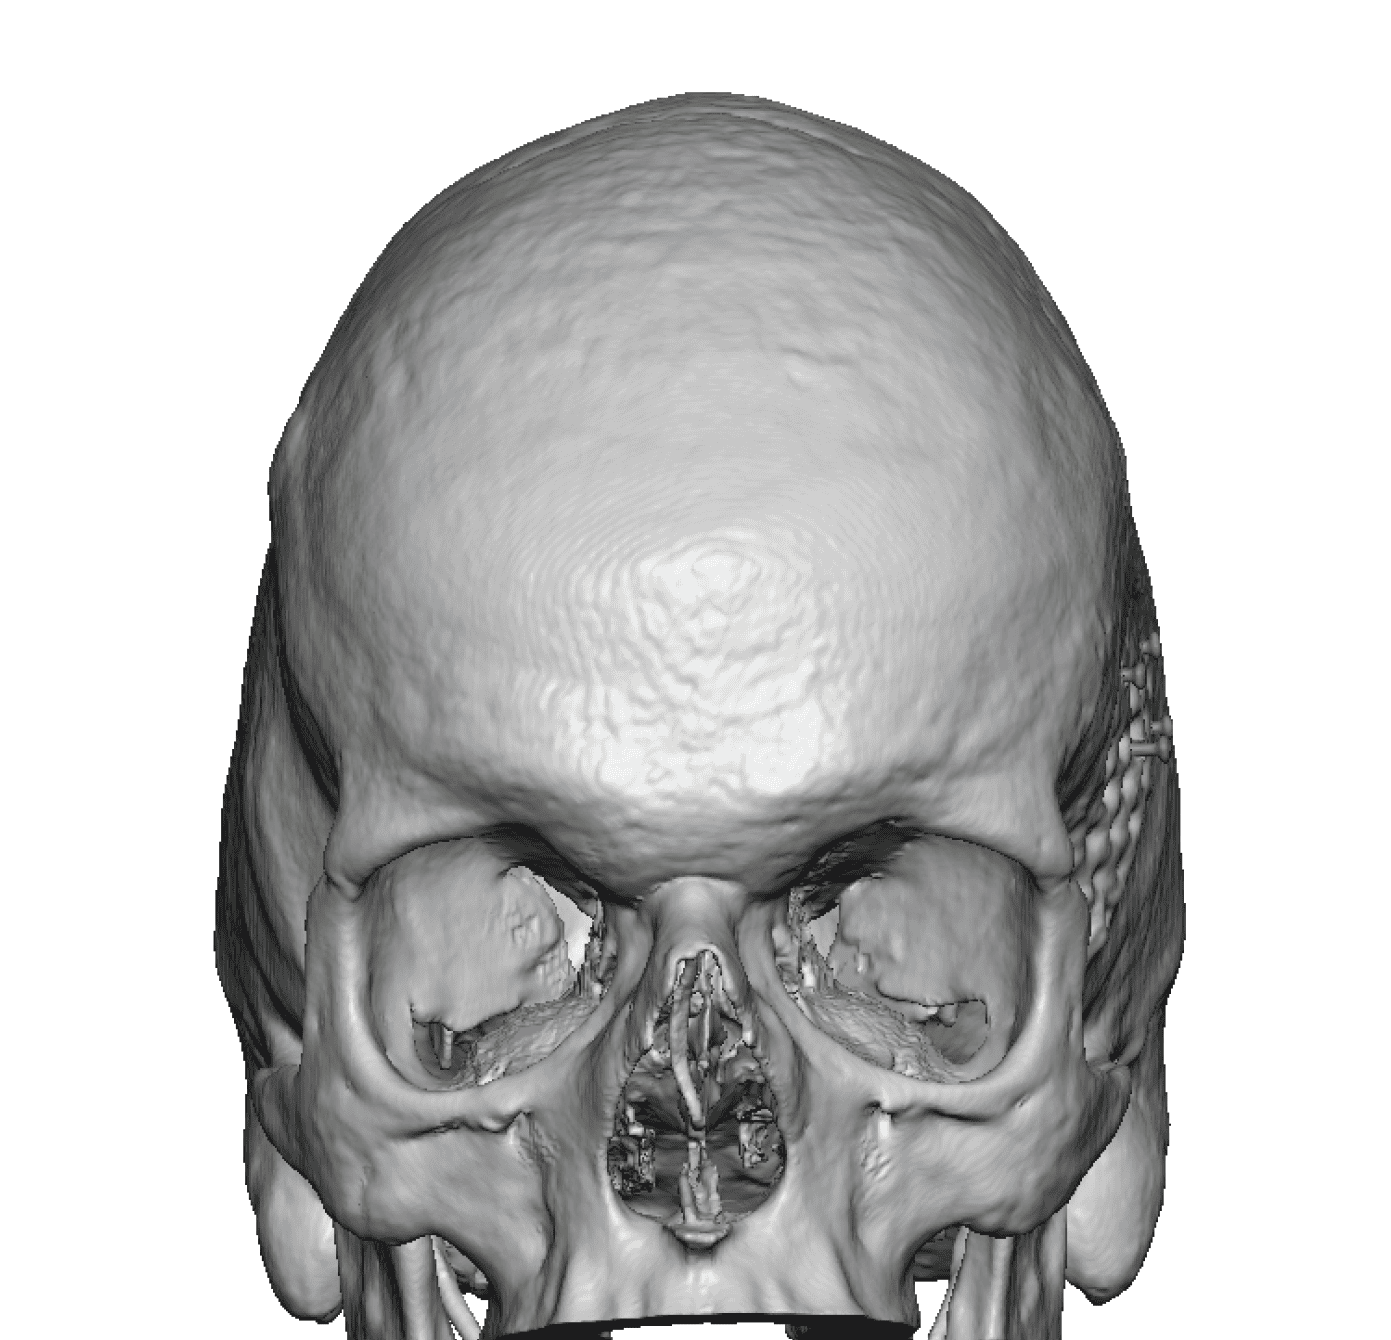

Desire for change of head shape from front view form an inverted V shape to a rounder and wider head shape.

Placement of custom extended forehead-temporal implants through incisions in the crease behind the ear. (he had a prior back of head skull implant which is green in the implant designs and which the head widening implants partially covered it)

Desire for change of head shape from front view form an inverted V shape to a rounder and wider head shape.

Placement of custom extended forehead-temporal implants through incisions in the crease behind the ear. (he had a prior back of head skull implant which is green in the implant designs and which the head widening implants partially covered it)